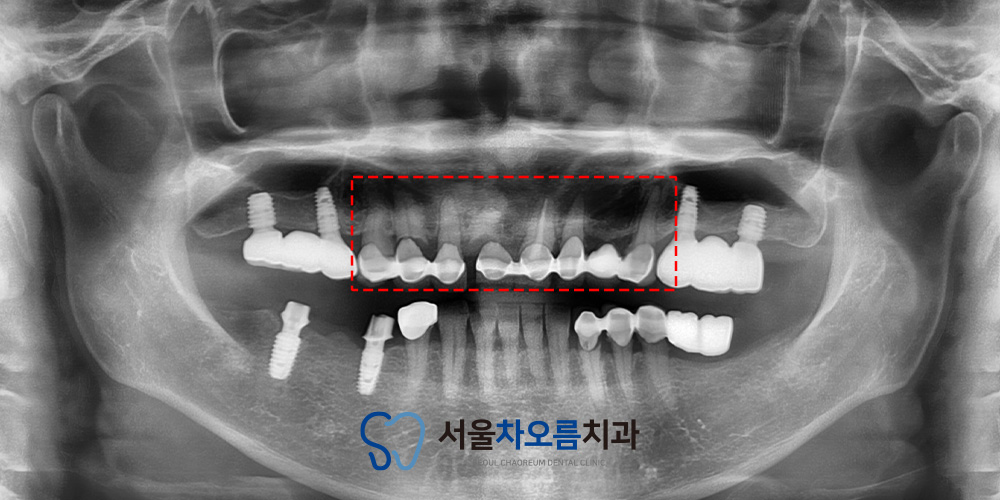

자세하게 확인하기 위해

파노라마를 촬영해보았습니다.

파노라마 상에서 기존 보철물 하방으로

충치가 진행된 양상이 확인되었고,

일부 치아에서는 치근 파절이

의심되는 소견도 함께 관찰되었습니다.

이로 인해 단순한 보철 교체만으로는

예후가 좋지 않을 것으로 판단되었습니다.

그래서 병점치과 365서울차오름에서는

앞니 브릿지 전체 제거 후

충치가 깊고 파절 및 인공치 부위는

임플란트를 진행하기로 하였습니다.

또한 비교적 상태가 유지된 잔존 치아들은

필요 시 신경치료를 시행한 후

크라운으로 마무리하여

기능과 심미성을 함께

회복하기로 하였습니다.